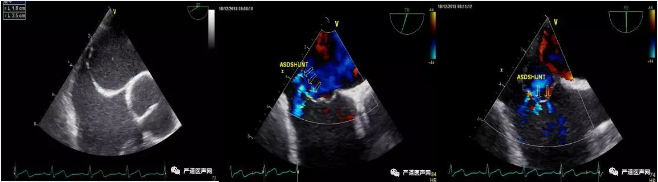

TEE结果

张玉顺教授团队详细分析研究患者病情后,认为介入封堵有90%以上的成功率。为了能更全面地了解房间隔缺损的解剖结构、提高手术成功率,予患者于结构性心脏病科进一步行食道超声检查。超声结果显示患者确系巨大房间隔膨出瘤,瘤底35mm,但瘤壁上可见6处筛孔样房缺,其中较大的一个5mm缺损位于后下方,其余均为2-3mm小孔。拿到检查结果的那一刻,张教授团队发现,手术的难度及复杂性远超预期设想,按照目前的结果,手术成功率可能仅为50%左右。张教授仔细分析超声结果后,认为该患者房间隔特点为:瘤腔大,瘤壁孔多而小,如果导丝进入偏上或偏下的孔,极易造成堵上堵不了下,堵下堵不了上的结局;而放置双伞的难度也极大,治疗效果不确定;如果导丝能精准入瘤腔中央的小孔,则可放置40mm特殊Amplazer筛孔ASD封堵器,这样既可最大程度的封堵所有的小孔,同时可夹闭整个薄弱的瘤壁。但手术的难点在于导丝、导管需要精准进入房间隔膨出瘤顶端中心位置的缺损,而此缺损仅为2mm,且位于瘤壁顶端,导丝及导管极难准确进入该孔。